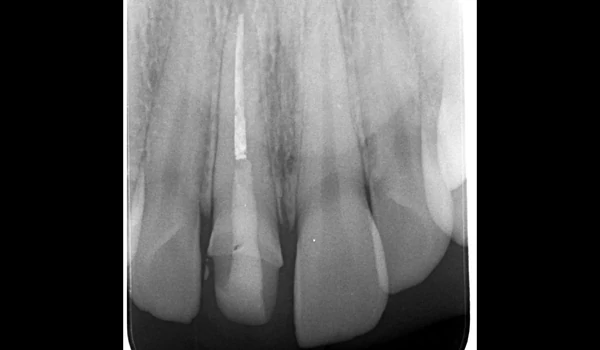

13. ábra. A kezelt fog intraorális periapikális röntgenfelvétele. |

3. Preparáció és digitális lenyomatA végleges restaurációhoz ¾-koronás preparációt végeztek, majd intraorális szkennert használtak lenyomatvételre. Ezt követően ideiglenes koronát készítettek, s árnyalatfotókat is rögzítettek kuraraynoritake.eu. |